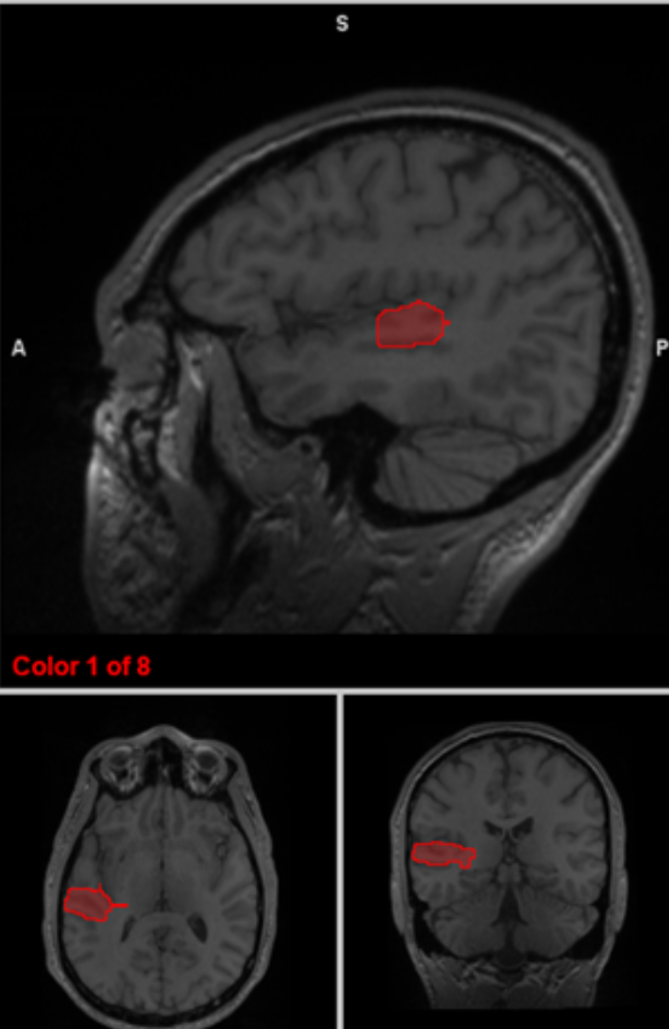

insular cortex

emotion